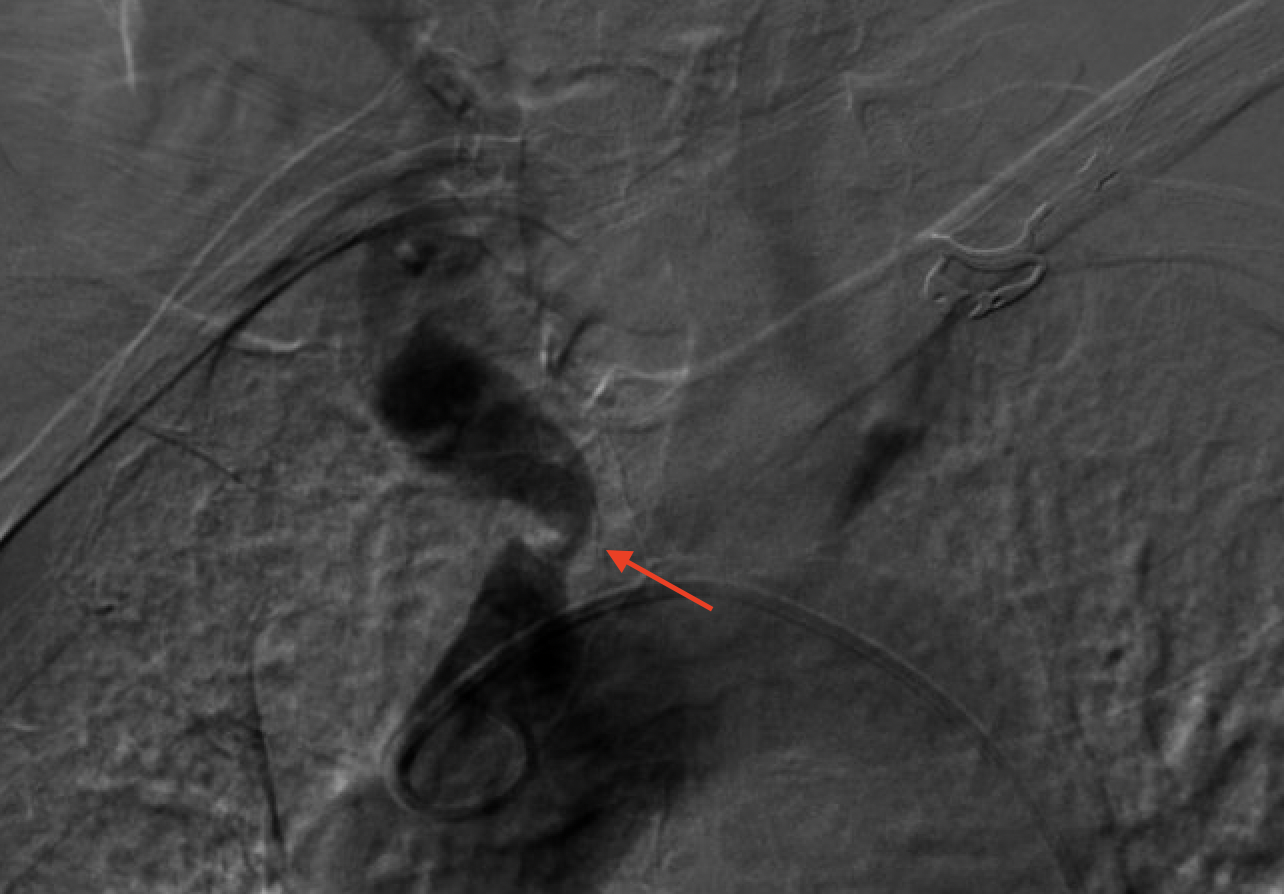

Considering the patient's comorbidities, an endovascular approach was the safest approach. Dual access was achieved using a 6F sheath in the right radial artery and another 6F sheath in the right femoral artery; an aortogram was then conducted showing severe stenosis in the right innominate artery (Figure 1). A carotid angiogram was performed, revealing a vessel size measuring 6 to 7 mm. We advanced a BareWire guidewire (Abbott Cardiovascular) and proceeded with the successful deployment of an Emboshield NAV6 filter (Abbott Cardiovascular) in the right ICA through the radial access as it was the only route for delivering it to prevent entrapment of the filter if placed from the femoral route (Figure 2).